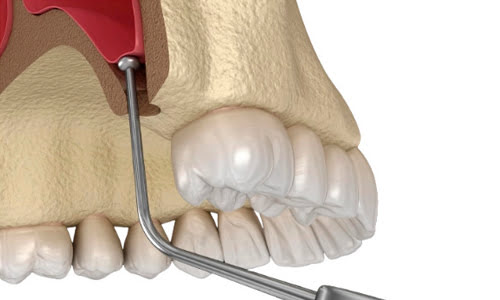

Soft Tissue Surgery

The soft tissue surgery course covers restorations that utilize surrounding soft tissue. The program introduces dentists to the background and surgical techniques involved in performing soft tissue surgery. With the completion of this course, dentists will learn the fundamentals involved in providing an efficient treatment plan of treating esthetic cases.